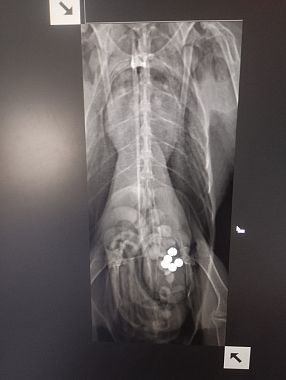

Dagli accertamenti veterinari è emerso che l’Avocetta ha lo stomaco pieno di pallini di piombo, ingeriti con ogni probabilità in modo accidentale mentre si alimentava sul fondo di una zona paludosa, suo habitat naturale. Durante la digestione, il piombo rilascia sostanze tossiche che provocano una grave intossicazione, debilitano l’animale e possono portarlo alla morte nel giro di pochi giorni.

I volontari e lo staff veterinario della Lipu Cruma Livorno - che garantiscono soccorso e assistenza a tutti gli animali in difficoltà anche nei giorni di festa - stanno sottoponendo l’Avocetta a una terapia chelante, necessaria per favorire l’eliminazione del piombo dall’organismo, e a una terapia di supporto alimentare.

"Se le condizioni lo permetteranno, nei prossimi giorni verrà effettuata anche una lavanda gastrica per rimuovere direttamente i pallini ancora presenti nello stomaco. In alternativa, si spera che l’animale riesca a espellerli naturalmente, evitando un’ulteriore assimilazione del metallo. - prosegue la nota - Il recupero sarà comunque lungo e delicato. Il piombo infatti permane a lungo nell’organismo e può causare ricadute gravi, compromettere la capacità di volo e di alimentazione autonoma".